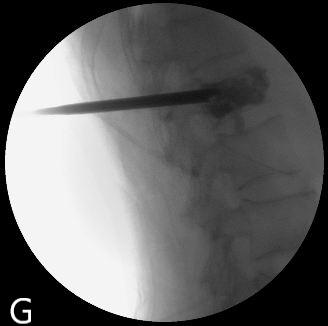

PVP是在影像引導(dǎo)下通過(guò)將穿刺針經(jīng)皮穿刺到病變椎體后向椎體內(nèi)注入骨水泥,以達(dá)到緩解腰背疼痛,增強(qiáng)椎體強(qiáng)度和穩(wěn)定性,防止塌陷,是部分恢復(fù)椎體高度的一種微創(chuàng)脊柱外科技術(shù)。PKP是在PVP的基礎(chǔ)上使用球囊擴(kuò)張椎體的技術(shù)。

圖為:南通瑞慈醫(yī)院骨科PVP術(shù)中影像

這兩種術(shù)式均是針對(duì)老年人設(shè)計(jì),具有創(chuàng)傷小,不需全身麻醉,術(shù)后恢復(fù)快等優(yōu)勢(shì),病人術(shù)后第二天就能下床活動(dòng)。南通瑞慈醫(yī)院骨科脊柱外科于2005年首次開(kāi)展此項(xiàng)技術(shù),如今已形成平均每年150例手術(shù)量規(guī)模,幫助諸多老年患者擺脫了疾病困擾。